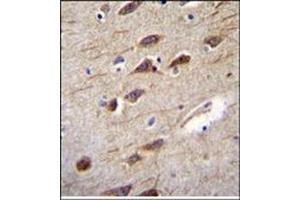

L’anticorps anti-RUSC2 Polyclonal Lapin est utilisé pour la détection de RUSC2 dans des échantillons de Humain. Il a été validé pour WB et IHC (p).

Western Blotting (WB), Immunohistochemistry (Paraffin-embedded Sections) (IHC (p))

WB: 1:1000. IHC-P: 1:50~100